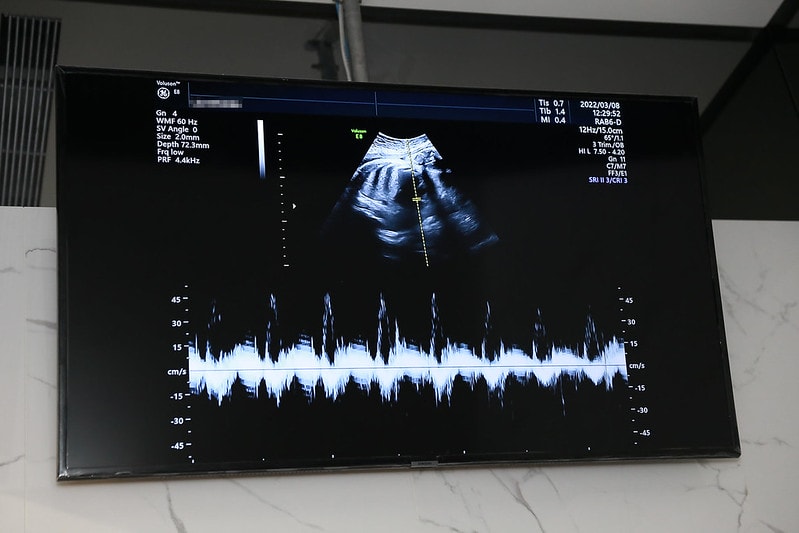

產檢就是會直接照超音波~

然後醫生檢查寶寶的大小

跟說目前胎兒發展的狀況

還有比方說頭圍大小阿

胎位正不正之類的狀態

小萊姆數據一直都滿正常的

大概七個月以後也就頭朝下,胎位是正的